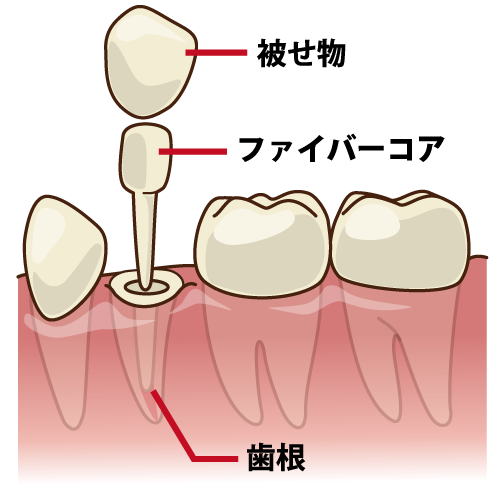

ファイバーコア:歯の「破折」を防ぐしなやかな土台

根の治療が終わった後、歯を補強するために「土台(コア)」を立てます。

当院では、歯の硬さに近く、適度なしなやかさを持つ「ファイバーコア」を推奨しています。

従来の金属の土台は硬すぎるため、強い力がかかった際に歯の根を折ってしまう(歯根破折)リスクがありました。

ファイバーコアは衝撃を吸収し、歯を根底から守ります。